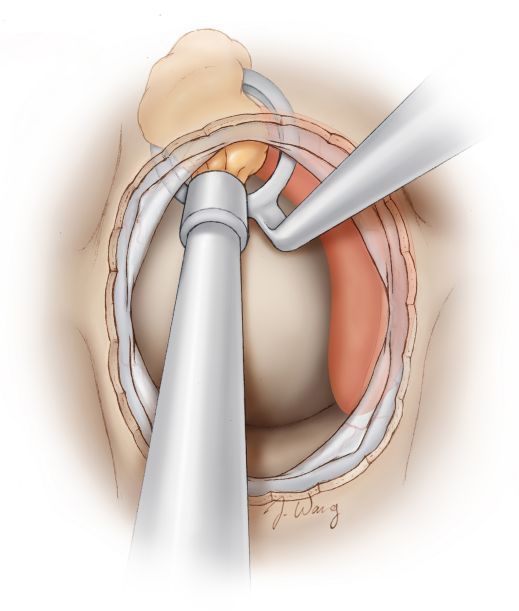

图7. 瘤内减压继而从肿瘤侧方进行,最后切除肿瘤上方部分。肿瘤大体减压后,从海绵窦后壁轻轻剥去肿瘤包膜。成角的内镜可扩展手术操作的视野,从而能在直视下从海绵窦侧壁分离肿瘤包膜,而不用环状刮匙盲刮肿瘤侧方。正常垂体在此视野下呈橙色。注意使用双手操作技术。(引自Tew, van Loveren, Keller*).

若肿瘤侵及海绵窦侧壁或鞍膈,可进行窦内及鞍上切除,操作时需谨慎。内镜扩展了手术视野,使用成角内镜可在直视下行海绵窦内肿瘤保守切除。(引自Tew, van Loveren, Keller*)